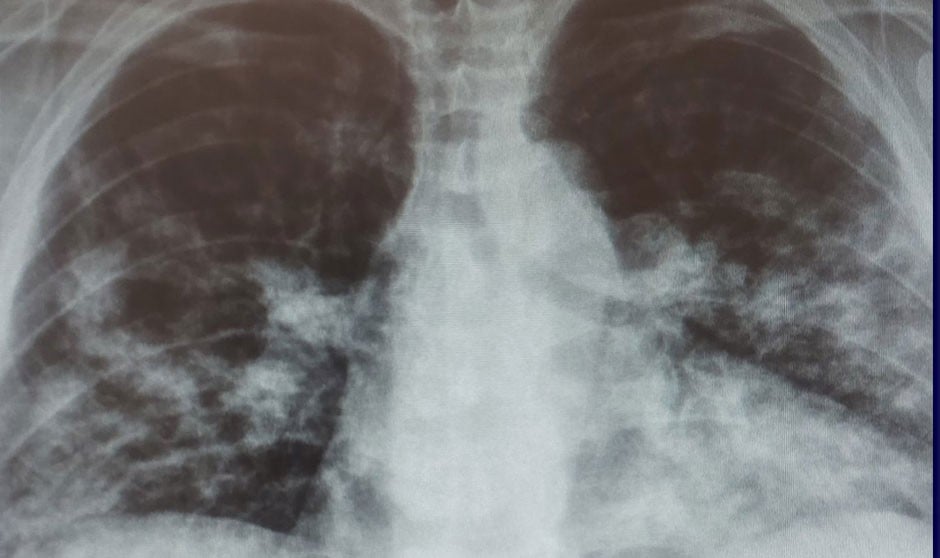

Un estudio en ratones demuestra el daño causado por las infecciones respiratorias en estos órganos

Algunas de las nuevas células basales se convierten en células productoras de moco, mientras que otras liberan moléculas que reclutan células inmunitarias en los pulmones. En conjunto, el proceso da lugar a pulmones con menos espacio aéreo, más mucosidad y una inflamación continua que, en conjunto, interfiere con la respiración.

Cambios pulmonares perjudiciales